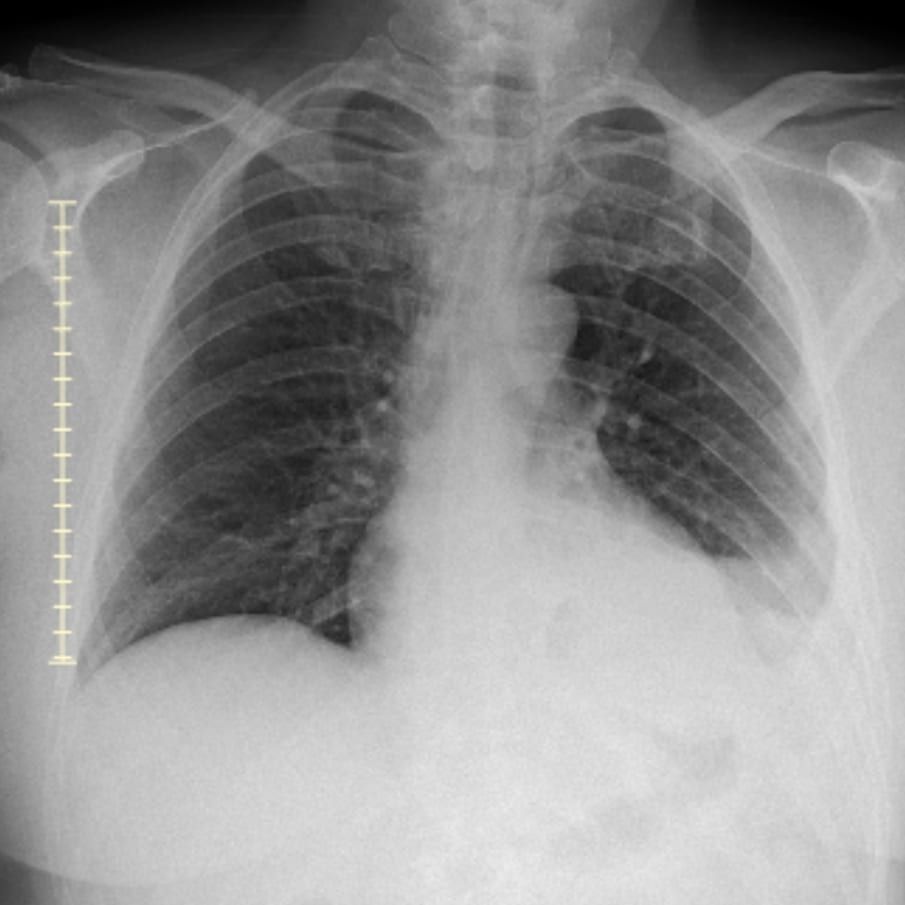

I got to the hospital emergency department and got seen. We spent about 6 hours there as they checked me and did chest x-rays and a CT scan. The hard part for me was laying down or taking in deep breaths. It was hard to breath, it just hurt when my chest expanded to a certain point.

After the tests, they didn’t find anything. The doctor did say my blood work hinted at a clot, but they didn’t see one. I also had a little fluid in a lung. Since they didn’t find anything, they suggested it may be muscle or skeletal related. The doctor prescribed me pain medication and a muscle relaxer.

The process was similar. I got brought in, and they did another chest x-ray and CT scan. This time, they saw a clot in each of my lungs. The ER doctor thanked me for listening to my body and coming in. They soon started me on heparin as I waited in the emergency department for a room to open up. I’m being admitted for observation and to do more testing.